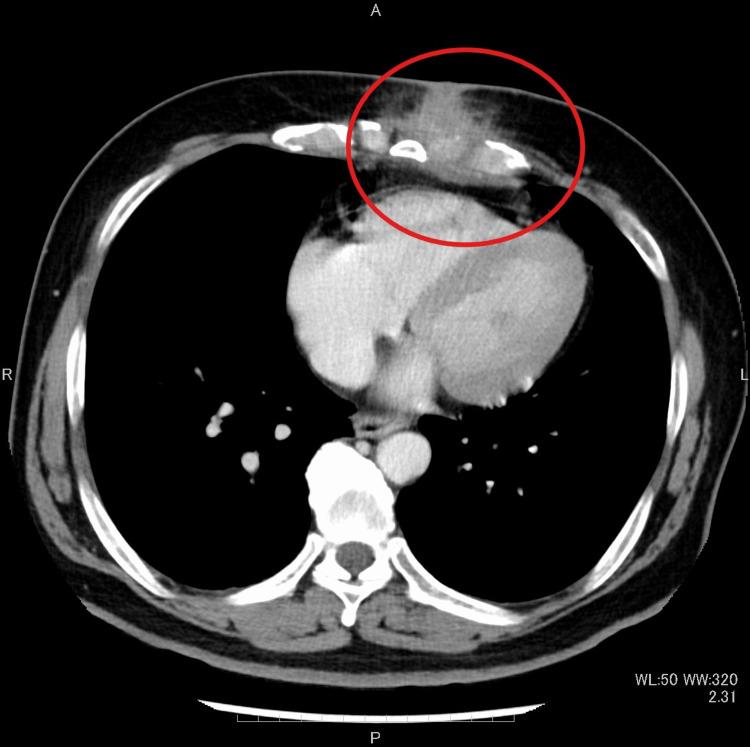

Costochondritis is primarily caused by physical exertion, repetitive movements (such as lifting heavy objects), and severe coughing. Although it is an inflammatory condition, it is not an infection and is often treated with non-steroidal anti-inflammatory drugs (NSAIDs). In contrast, infectious costochondritis usually develops when an infection spreads directly from a postoperative wound or adjacent foci. We present a case of infectious costochondritis with sternal osteomyelitis caused by , where the infection did not spread from adjacent tissues. A 59-year-old man was referred to our hospital with anterior chest pain and swelling persisting for three months. He had been diagnosed with diabetes mellitus three years prior. Three weeks before his visit, a purulent exudate had fistulized into the skin. Two weeks prior, he had sought care from a nearby doctor, who diagnosed a subcutaneous abscess and performed an incision and drainage. Cultures identified . However, the condition did not improve, and chest computed tomography (CT) was performed, showing edema around the seventh costal cartilage, the inferior end of the sternum, and surrounding subcutaneous tissue. Distraction of the seventh costal cartilage was also noted. Magnetic resonance imaging (MRI) with fat-suppressed T2-weighted images showed high intensity in the same area. Blood cultures were negative. Based on these findings, we diagnosed costochondritis and sternal osteomyelitis. Treatment began with oral cefalexin (CEX) for seven days, followed by oral cefcapene pivoxil hydrochloride hydrate (CFPN-PI) for 14 days. During hospitalization, meropenem hydrate (MEPM) was administered. After seven days of MEPM, the seventh costal cartilage and part of the sternum were debrided under general anesthesia. Indicators of the extent of debridement included preoperative MRI, bone cortex hardness under intraoperative palpation, and bone bleeding. MEPM was administered for 14 days, including preoperative treatment, followed by cefepime dihydrochloride hydrate (CFPM) for 14 days and levofloxacin hydrate (LVFX) for seven days. After 11 months of follow-up, there was no recurrence of costochondritis or osteomyelitis. Infectious costochondritis with sternal osteomyelitis caused by was successfully treated with debridement. Properly determining the extent of debridement perioperatively is crucial for effective treatment.

肋软骨炎主要由体力活动、重复性动作(如提重物)和剧烈咳嗽引起。虽然它是一种炎症性疾病,但不是感染性疾病,通常用非甾体抗炎药(NSAIDs)治疗。相比之下,感染性肋软骨炎通常在感染从术后伤口或邻近病灶直接蔓延时发生。我们报告一例由[具体病因未给出]引起的伴有胸骨骨髓炎的感染性肋软骨炎病例,感染并非从邻近组织蔓延而来。一名59岁男性因前胸疼痛和肿胀持续三个月被转诊至我院。他三年前被诊断患有糖尿病。就诊前三周,脓性渗出物形成瘘管通向皮肤。两周前,他曾到附近医生处就诊,医生诊断为皮下脓肿并进行了切开引流。培养结果鉴定出[具体病菌未给出]。然而,病情并未改善,遂进行胸部计算机断层扫描(CT),显示第七肋软骨、胸骨下端及周围皮下组织水肿。还注意到第七肋软骨有分离。脂肪抑制T2加权磁共振成像(MRI)显示同一区域呈高强度信号。血培养结果为阴性。基于这些发现,我们诊断为肋软骨炎和胸骨骨髓炎。治疗开始时口服头孢氨苄(CEX)7天,随后口服头孢丙烯水合物(CFPN-PI)14天。住院期间给予美罗培南水合物(MEPM)。使用MEPM 7天后,在全身麻醉下对第七肋软骨和部分胸骨进行清创。清创范围的指标包括术前MRI、术中触诊时骨皮质硬度以及骨出血情况。MEPM使用14天,包括术前治疗,随后使用头孢吡肟二盐酸盐水合物(CFPM)14天和左氧氟沙星水合物(LVFX)7天。经过11个月的随访,肋软骨炎和骨髓炎均未复发。由[具体病因未给出]引起的伴有胸骨骨髓炎的感染性肋软骨炎通过清创成功治愈。围手术期正确确定清创范围对于有效治疗至关重要。